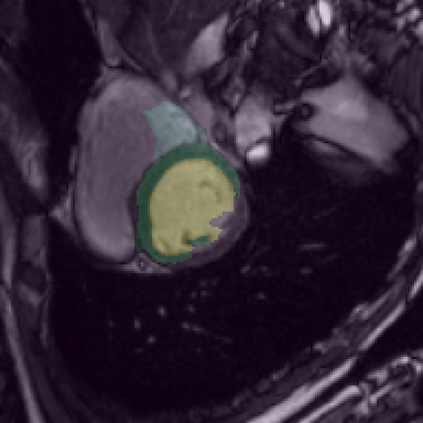

Supervised deep learning-based methods yield accurate results for medical image segmentation. However, they require large labeled datasets for this, and obtaining them is a laborious task that requires clinical expertise. Semi/self-supervised learning-based approaches address this limitation by exploiting unlabeled data along with limited annotated data. Recent self-supervised learning methods use contrastive loss to learn good global level representations from unlabeled images and achieve high performance in classification tasks on popular natural image datasets like ImageNet. In pixel-level prediction tasks such as segmentation, it is crucial to also learn good local level representations along with global representations to achieve better accuracy. However, the impact of the existing local contrastive loss-based methods remains limited for learning good local representations because similar and dissimilar local regions are defined based on random augmentations and spatial proximity; not based on the semantic label of local regions due to lack of large-scale expert annotations in the semi/self-supervised setting. In this paper, we propose a local contrastive loss to learn good pixel level features useful for segmentation by exploiting semantic label information obtained from pseudo-labels of unlabeled images alongside limited annotated images. In particular, we define the proposed loss to encourage similar representations for the pixels that have the same pseudo-label/ label while being dissimilar to the representation of pixels with different pseudo-label/label in the dataset. We perform pseudo-label based self-training and train the network by jointly optimizing the proposed contrastive loss on both labeled and unlabeled sets and segmentation loss on only the limited labeled set. We evaluated on three public cardiac and prostate datasets, and obtain high segmentation performance.